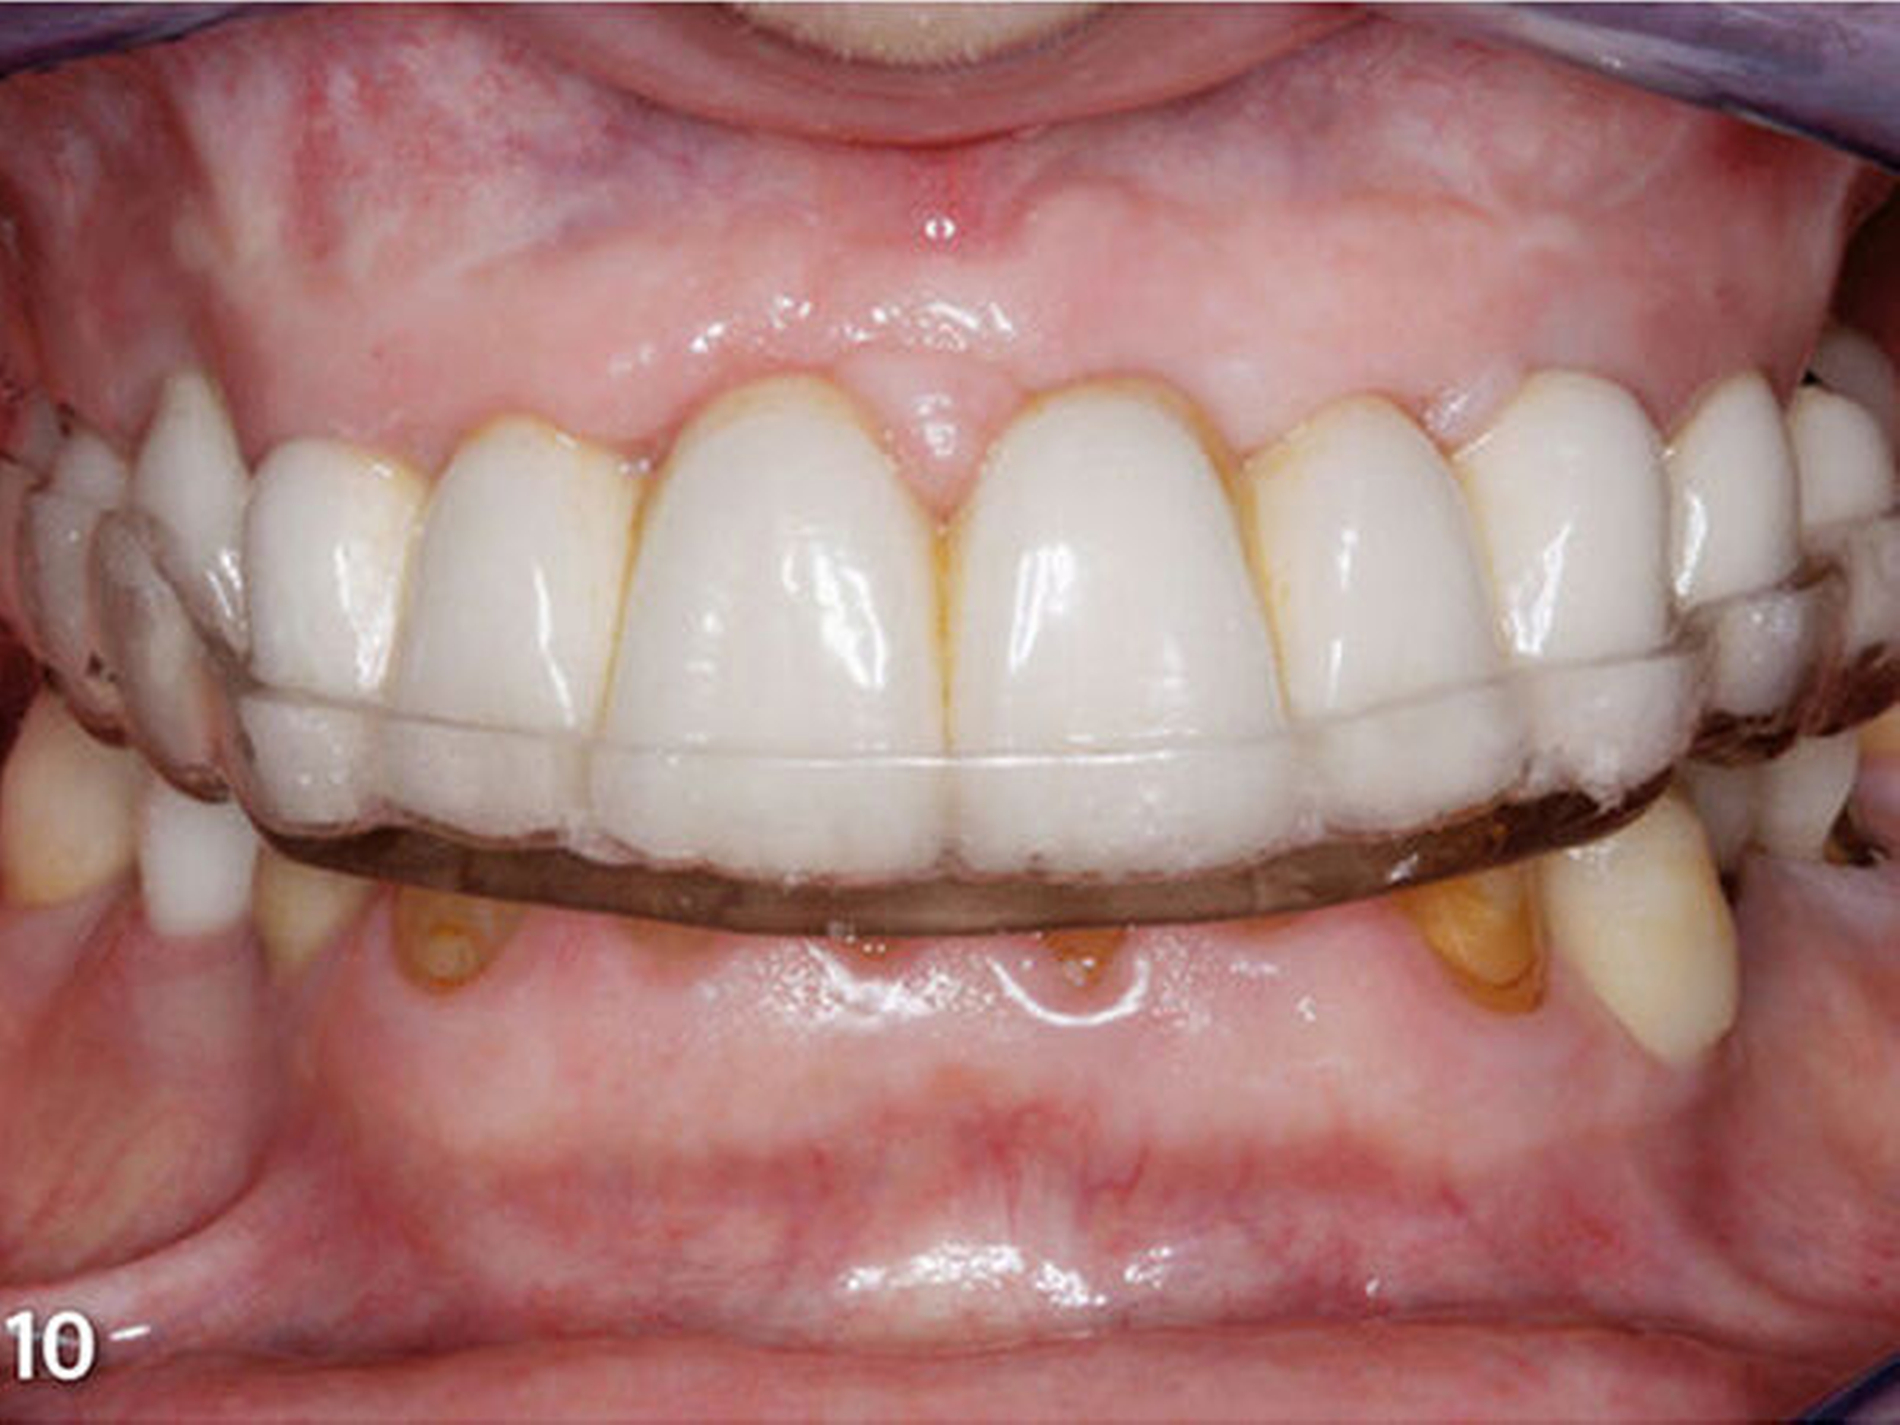

Dritte zahnärztliche Sitzung: Der Patientin wurde die stabilisierende Okklusionsschiene eingegliedert, und sie wurde in den Gebrauch der Apparatur eingewiesen (Abb.10). Die Passung der Schiene und die Adaptation der Patientin an die Apparatur wurden einen Tag, eine Woche und zwei Wochen nach der Eingliederung an weiteren Kontrollterminen geprüft. Bei den ersten beiden dieser Termine wurden geringfügige Änderungen an der statischen und dynamischen Okklusion der Schienenoberfläche vorgenommen. Diese funktionelle Evaluationsphase dauerte insgesamt sechs Wochen. Während dieser Zeit trug die Patientin die Schiene für 24 Stunden am Tag, lediglich zur Nahrungsaufnahme und für die Mundhygiene wurde die Apparatur herausgenommen (Muts et al. 2014; Rammelsberg 2014). Treten initiale Adaptationssymptome und Beschwerden wegen der Okklusionsschiene auf, verschwinden diese im Regelfall innerhalb von ein bis zwei Wochen wieder (Carlsson et al. 1979; Dahl & Krogstad 1982; Gross & Ormianer 1994). Daher ist es sinnvoll, einen Zeitraum von einigen Wochen für die Simulationsphase vor dem Übergang zum nächsten Therapieschritt anzusetzen (Abduo 2012; Abduo & Lyons 2012). Das Anheben der Vertikaldimension sollte vorzugsweise mit einem fest sitzenden Therapiemittel erfolgen, da es die Funktion, Akzeptanz und Adaptation des Patienten verbessert. Herausnehmbare Schienen resultieren in mehr Beschwerden und Symptomen, die aber eher auf das Tragen der Schiene als auf die Anhebung der Vertikaldimension zurückzuführen scheinen (Abduo 2012; Abduo & Lyons 2012).